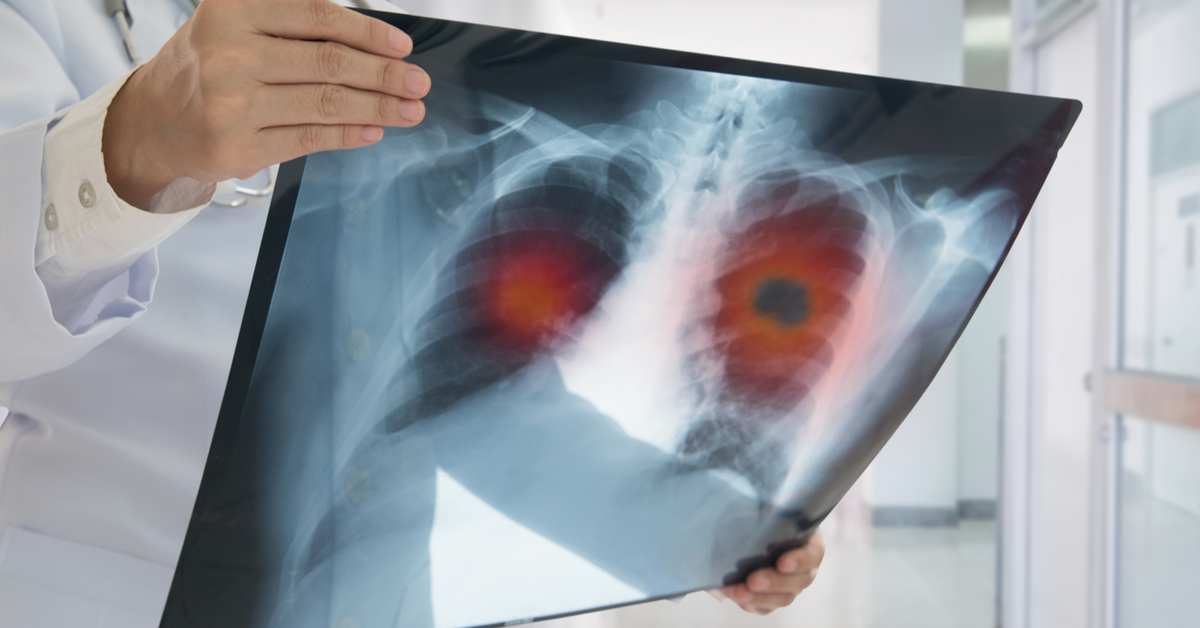

9 أعراض قد تكون من العلامات المبكرة لسرطان الرئة

يعد سرطان الرئة من أكثر السرطانات شيوعا بين الرجال والنساء على حد سواء، حيث ترتبط أسبابه بشكل وثيق بعوامل مثل التدخين، وتلوث الهواء، والتعرض للمواد السامة.

وتشير بيانات إلى أن حالات الإصابة والوفيات بسرطان الرئة تسجّل ارتفاعا ملحوظا في العديد من الدول، مما يفرض تحديات متزايدة على الأنظمة الصحية ويعيد فتح النقاش حول أهمية الوقاية والكشف المبكر.

وقالت الدكتورة جيني ماسنجر، استشارية أمراض الجهاز التنفسي والطب العام: "التدخين هو السبب الرئيسي للإصابة بسرطان الرئة، لكن يمكن أيضا أن تكون له أسباب جينية، إلى جانب التلوث، والسمنة، والتعرض للمواد الكيميائية في أماكن العمل".

وغالبا ما يشخص سرطان الرئة باستعمال التصوير المقطعي للصدر، كما أن له أعراضا تمكن من الكشف المبكر عن هذا المرض الخبيث.